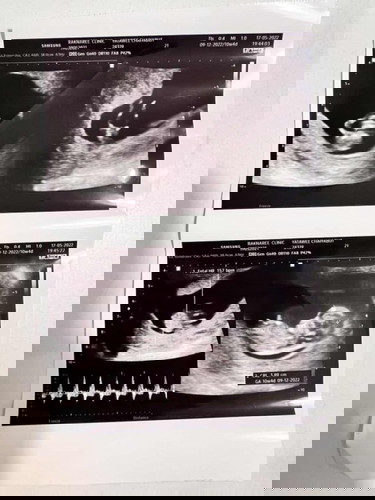

สวัสดีค่ะ ตอนนี้อายุครรภ์ได้ 8w เมื่อ2วันก่อนมีเลือดออกสีแบบในภาพเลยคะจึงไปหาคุณหมอ คุณหมอก็แจ้งว่าน่าจะเป็นเลือดเก่า จึงให้กลับมานอนพัก 2 วันไม่ได้ให้ยาหรือฉีดยาอะไร ซาวดูน้องปกติดีคะหังใจเต้นดี ถุงน้ำกลมสวยดี แล้วเมื่อวานเลือดก็หายไปแล้วค่ะ พอเช้าวันนี้มีเลือดแบบนี้ออกมาอีก แม่ ๆ ท่านไหนเคยเป็นแบบนี้บ้างคะ ทำยังไงกันบ้าง #ขอบคุณล่วงหน้านะคะ #คุณแม่ๆช่วยแนะนำหน่อยค่ะ #ท้องแรก #ขอบคุณสำหรับคำตอบค่ะ